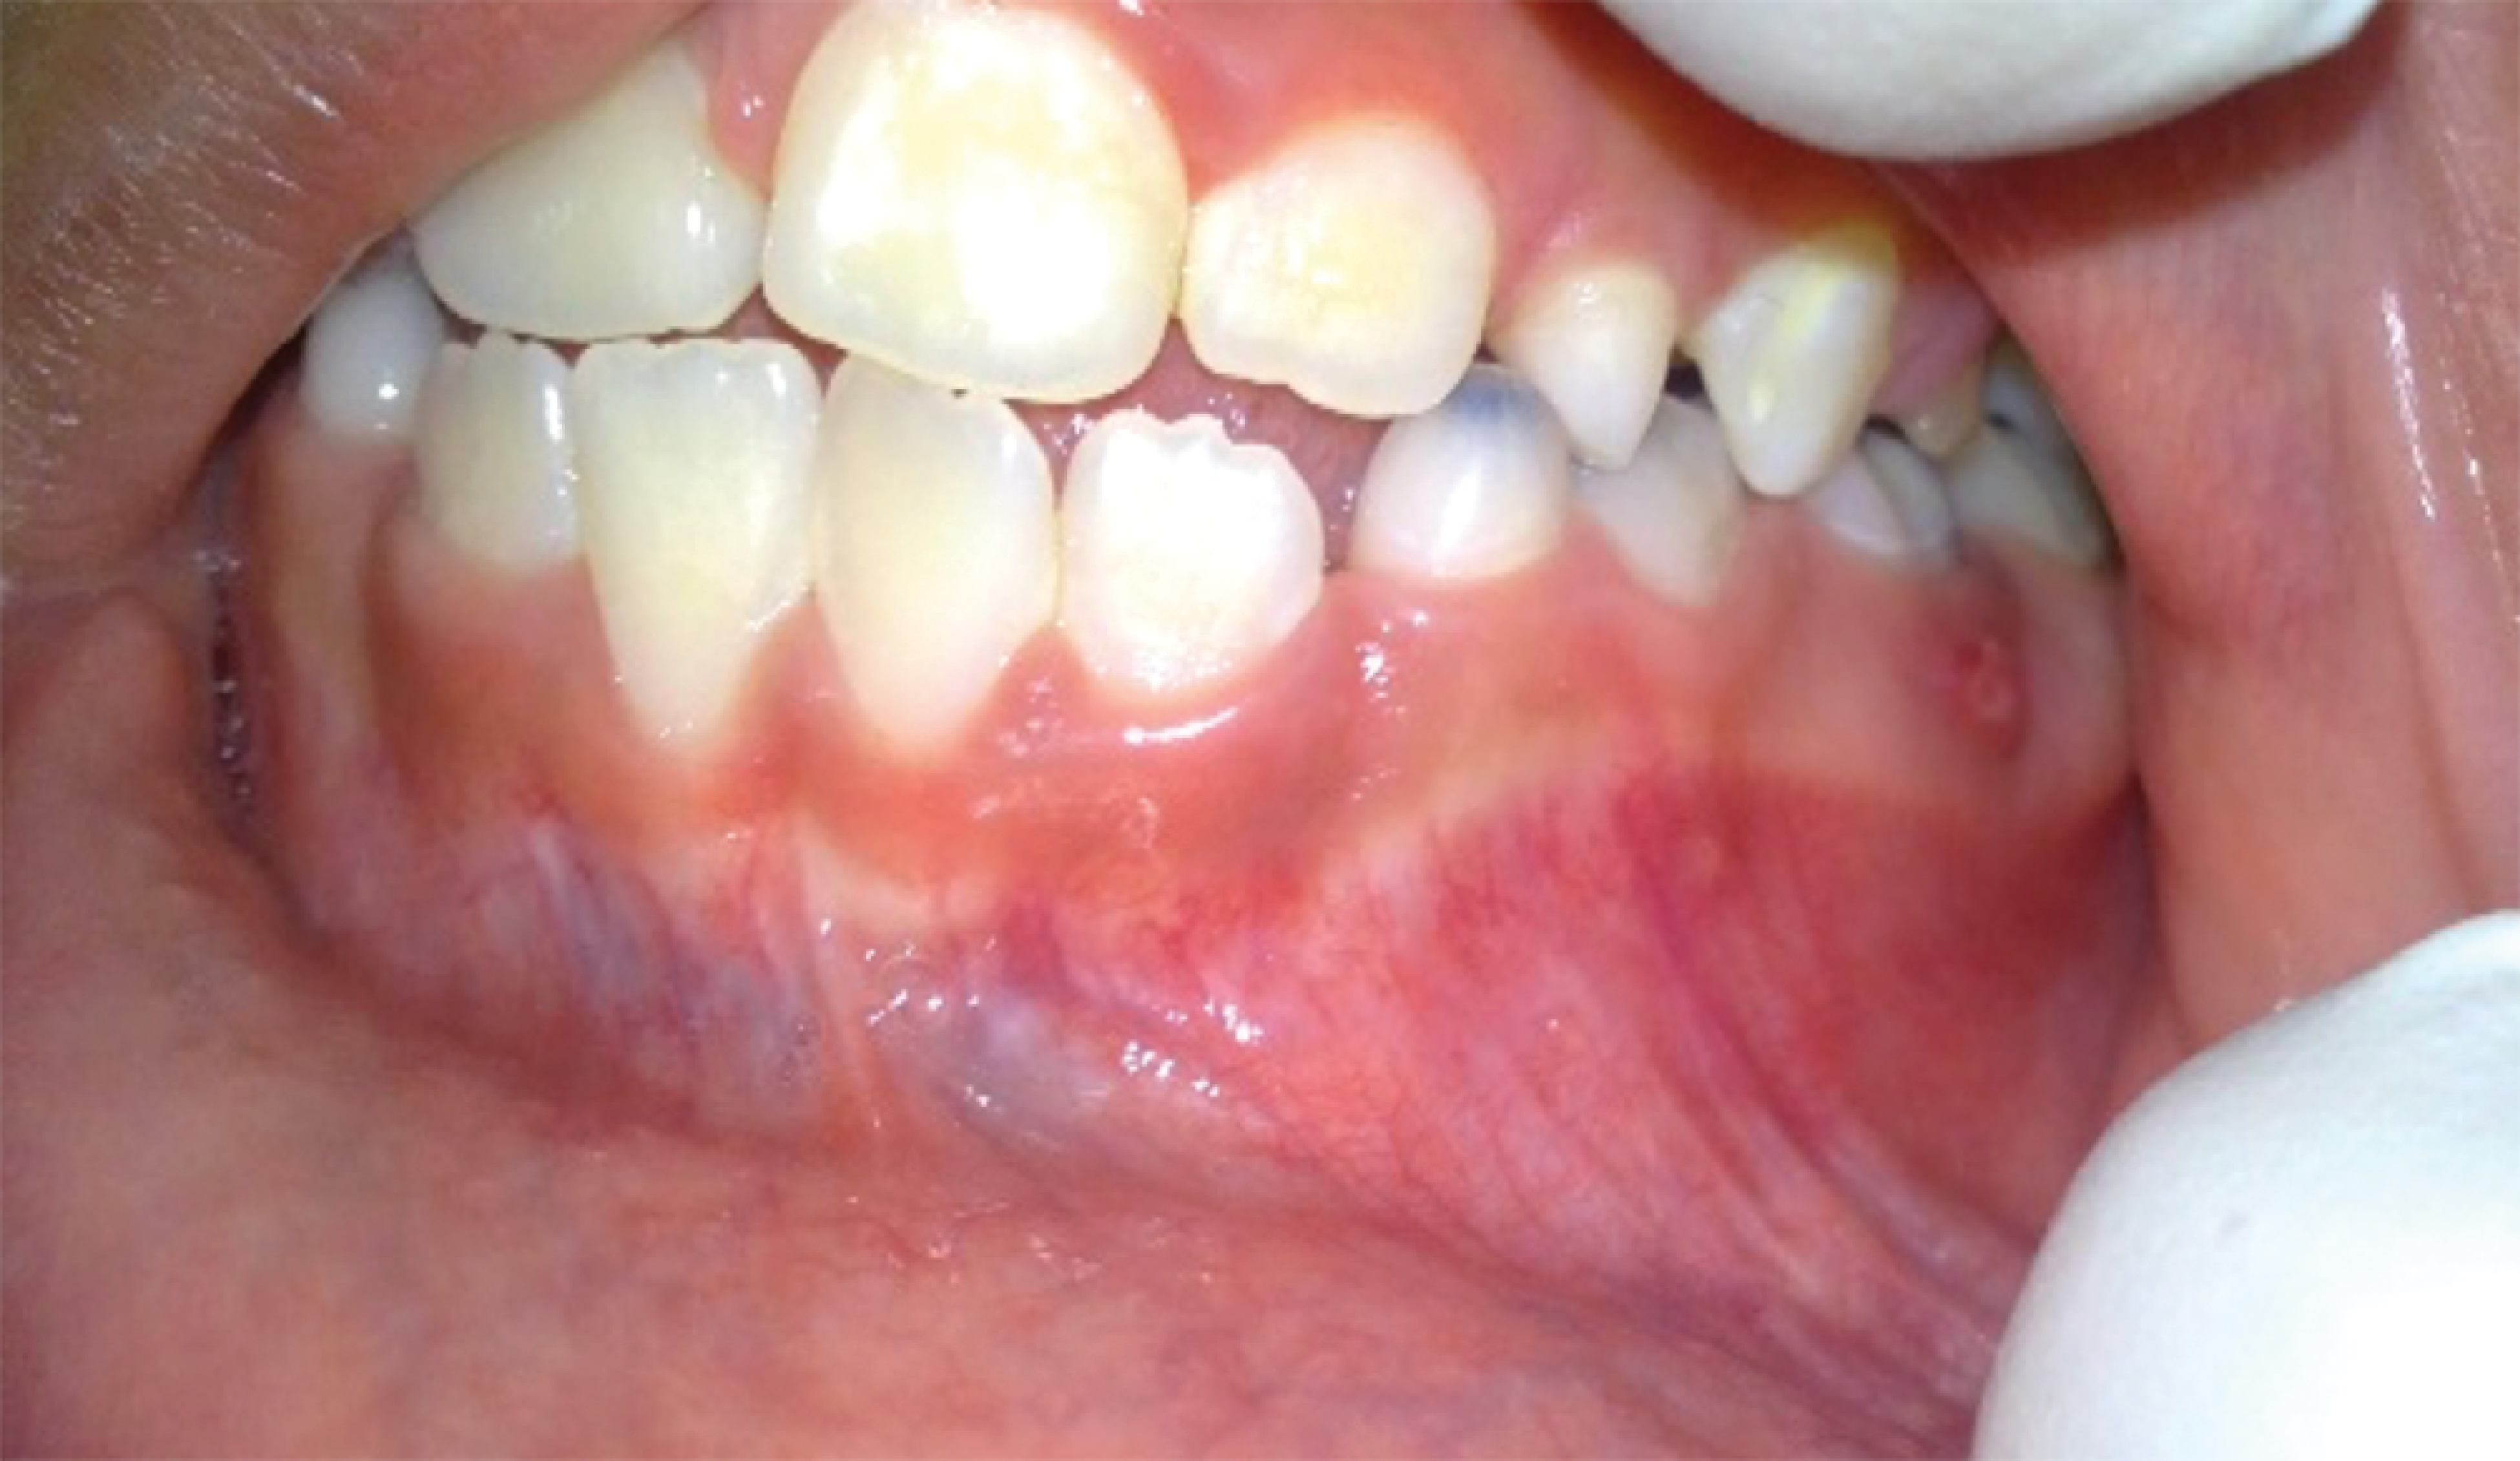

Figure 1